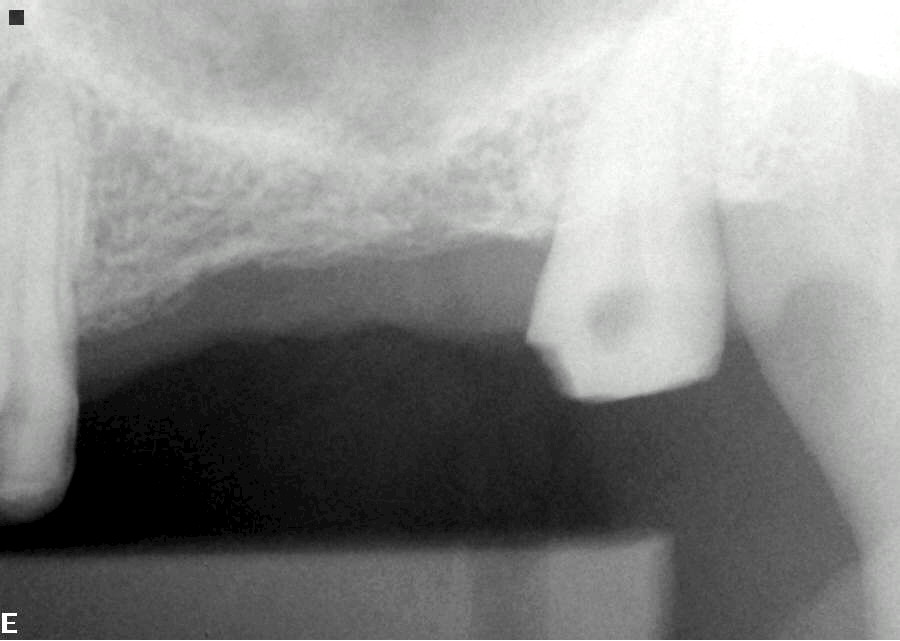

Orthodontic Treatment X-ray - After